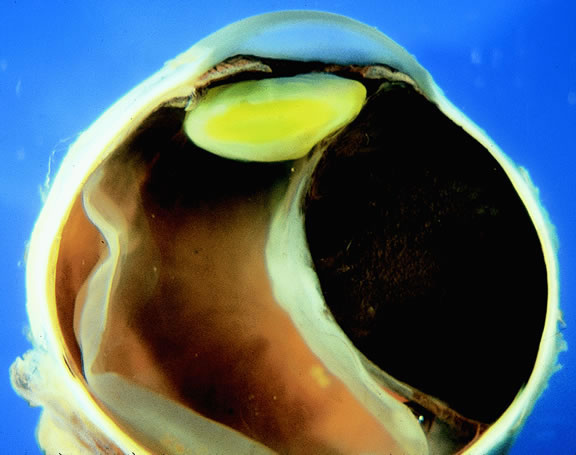

Most eyes with untreated uveal melanoma eventually develop glaucoma.74,75 Anterior tumors, that is, high-grade iris melanomas or ciliary body melanomas that invade the anterior chamber, typically cause secondary open-angle glaucoma by seeding or directly infiltrating the trabecular meshwork (Fig. 12). The latter often occurs in a circumferential or ring fashion. Posterior melanomas generally cause secondary angle closure glaucoma by stimulating iris neovascularization or by causing pupillary block. The pupil is blocked when large tumors or tumors that have caused highly elevated total retinal detachments displace the lens iris diaphragm forward (Fig. 13). The same mechanism also occurs in eyes with other neoplasms that typically are associated with high bullous retinal detachments such as uveal metastases, choroidal hemangiomas, and exophytic retinoblastomas. In such cases, severe pain often prompts a patient with a blind eye to seek medical care. More than a century ago, it initially was emphasized that a glaucomatous eye with a total retinal detachment harbors an intraocular tumor, typically a melanoma, until proven otherwise. Imaging studies such as ultrasonography are mandatory before therapy in such cases, especially if evisceration of a blind painful eye is contemplated instead of enucleation.

Fig. 13. Large ciliochoroidal melanoma with total retinal detachment and secondary closed-angle glaucoma caused by anterior displacement of lens-iris diaphragm.

Retinal detachment is the most common cause of visual loss in eyes with posterior melanoma. Initially solid, the detachment becomes exudative as serous fluid accumulates. Visual loss initially may be caused by induced hyperopia as a subfoveal tumor displaces the retina anteriorly. The exudative detachment initially is localized; fluid accumulates in the subretinal space tented up by the growing tumor. Failure to find a retinal hole in a patient with retinal detachment should always raise the possibility of a choroidal tumor or some other choroidal process known to produce an exudative detachment. Total retinal detachments are found in some eyes with choroidal melanomas, generally those with larger or neglected tumors (see Fig. 13). Melanoma-bearing eyes with total retinal detachments often have secondary closed-angle glaucoma caused by pupillary block or iris neovascularization.74,75 Clumps of orange pigment may be seen in the subretinal space overlying the tumor (see Fig. 40).